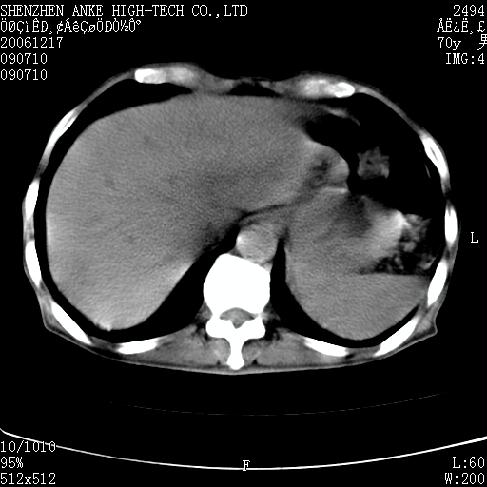

患者:男,70岁,腹部疼痛待查.b超见左肾脏占位待排.因为患者经济条件不好,没有做增强.

支持胰腺癌伴肝转移;左肾囊肿?

胰尾与左肾上缘部位见有一肿块影,密度不均匀,周围边界不清晰,与胰腺相连,与左肾边界不清,肝脏内见有多发低密度影,考虑胰尾癌伴左肾侵犯并肝内转移。最好是做个增强。

考虑:1,胰腺癌伴肝转移;2,左肾小囊肿。

与胃、脾及左肾之间见一巨大肿块影,其内密度不均,边界欠清,与胰腺关系密切。肝实质内见多个类圆形低密度灶,边界较清。符合胰腺癌并肝转移表现。

考虑:1,胰腺癌伴肝转移;2,左肾小囊肿. 3胰腺病变与左肾分界不清,肾脏可能受累。

与胃、脾及左肾之间见一巨大肿块影,其内密度不均,边界欠清,与胰腺关系密切。肝实质内见多个类圆形低密度灶,边界较清。符合胰腺癌并肝转移表现。

同意胰尾部癌累及左肾前,肝多发转移,左肾小囊肿。

胰尾与左肾上缘部位见有一肿块影,密度不均匀,周围边界不清晰,与胰腺相连,与左肾边界不清,肝脏内见有多发低密度影,考虑胰尾癌伴左肾侵犯并肝内转移。最好是做个增强。